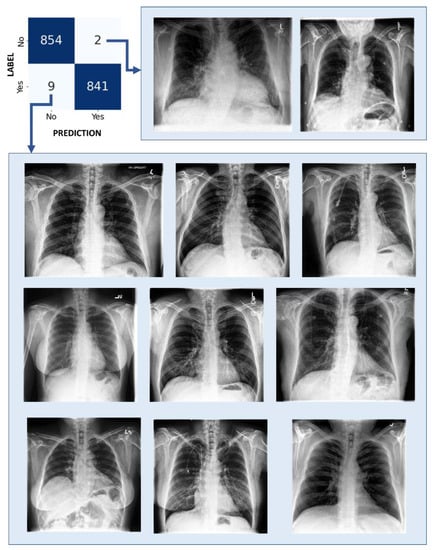

3.4. Grad-CAM++ Analysis

| Heatmap Pattern | Label | CC Model | CQ Model (Qiskit) | CQ Model (PennyLane) |

|---|---|---|---|---|

| Trustworthy | Control | 209 | 354 | 342 |

| Cardiomegaly | 237 | 330 | 326 | |

| Total | 446 (61%) | 684 (94%) | 668 (92%) | |

| Non-trustworthy | Control | 160 | 15 | 27 |

| Cardiomegaly | 124 | 31 | 35 | |

| Total | 284 (39%) | 46 (6%) | 62 (8%) |